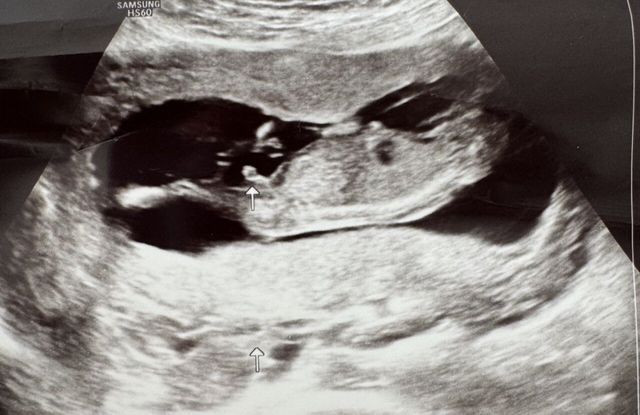

임신 사실은 알고있었지만

바라던바가 있었는데 오늘 그 바램이 이루어졌네요

육안으로 아들이라네요 ㅎㅎㅎㅎ

첫째둘째 다 딸이라 아들 간절했는데

저도 늦둥이 아들아빠 됬습니다